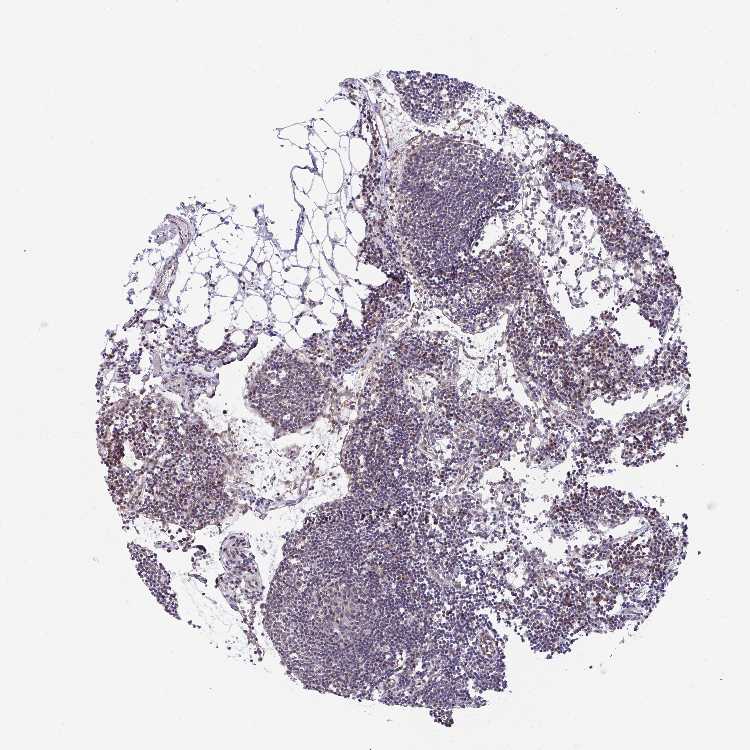

C5orf24